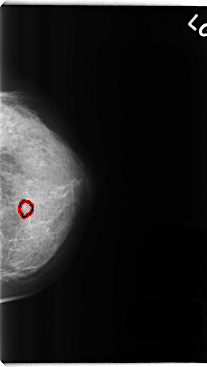

C_0257_1.LEFT_CC

FILE: C_0257_1.LEFT_CC.OVERLAY

TOTAL_ABNORMALITIES 1

ABNORMALITY 1

LESION_TYPE CALCIFICATION TYPE ROUND_AND_REGULAR DISTRIBUTION CLUSTERED

ASSESSMENT 3

SUBTLETY 5

PATHOLOGY BENIGN

TOTAL_OUTLINES 1

BOUNDARY

LEFT_CC LINES 4768 PIXELS_PER_LINE 2680 BITS_PER_PIXEL 12 RESOLUTION 50 OVERLAY